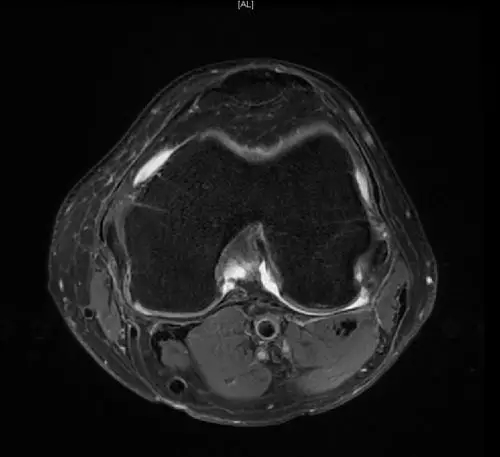

后交叉韧带断裂

从此片可以看出后交叉韧带连续性中断,松弛,增粗,下止点信号增高比较明显,从这个角度看后交叉韧带上止点信号较为正常,但下止点信号明显增高,缺乏韧带止点应有的形态,从这个层面看下止点信号增高,从这个层面看韧带是增粗的,整体信号增高,质地不均一,并且松弛,从这个层面可以看到它的下止点信号增高,缺乏正常的韧带形态特点,所以考虑后交叉韧带断裂。